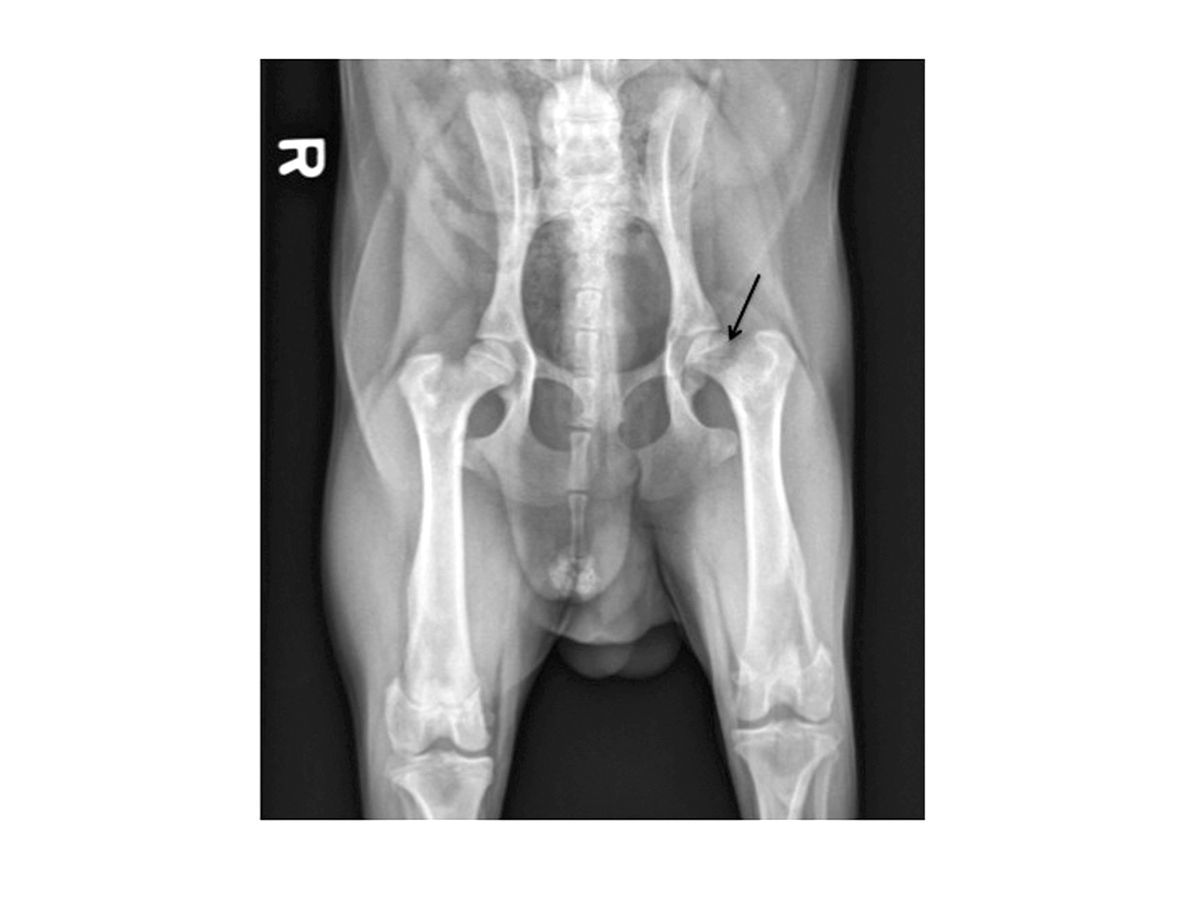

Anche se i riscontri dell’esame clinico, unitamente al classico segnalamento, sono fortemente suggestivi della Legg-Calvé-Perthes, si eseguono solitamente radiografie come evidenza di supporto a questa condizione. Inizialmente, possono essere presenti aree di lisi e demineralizzazione nella regione subcondrale della testa e del collo femorali (Figura 1). Mentre la condizione progredisce, può apparire un evidente collasso della testa e del collo femorali (Figura 2). Più avanti nel decorso della malattia, può essere presente un’evidenza di rimineralizzazione e guarigione dell’osso. Possono essere osservate alterazioni osteoartritiche secondarie, tra cui la formazione di osteofiti (in particolare lungo la rima acetabolare dorsale e la testa femorale) e l’appiattimento della testa femorale.

Radiografia di un cane che mostra le tipiche alterazioni iniziali della Legg-Calvé-Perthes. La freccia indica le aree di demineralizzazione precoce.

Figura 1. Radiografia di un cane che mostra le tipiche alterazioni iniziali della Legg-Calvé-Perthes. La freccia indica le aree di demineralizzazione precoce.© Darryl L. Millis